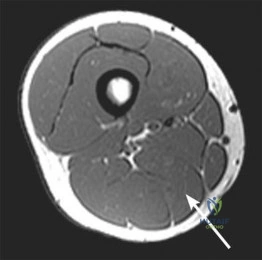

Question 5:

During a surgical approach for a highly comminuted talar body fracture, the surgeon notes damage to the artery of the tarsal canal. This artery is the predominant blood supply to the talar body. From which parent vessel does it originate?

Options:

- Anterior tibial artery

- Posterior tibial artery

- Peroneal artery

- Dorsalis pedis artery

- Lateral plantar artery

Correct Answer: Posterior tibial artery

Explanation:

The artery of the tarsal canal is a branch of the posterior tibial artery and supplies the majority of the talar body. It forms an anastomotic sling with the artery of the sinus tarsi (which arises from branches of the perforating peroneal and anterior lateral malleolar arteries).